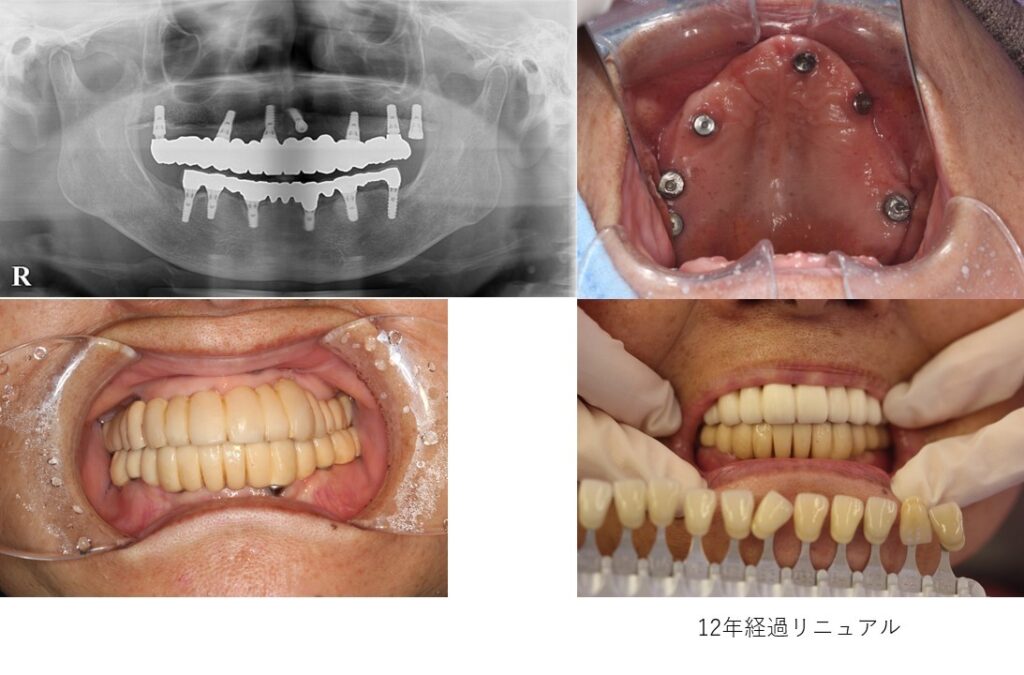

症例集

天然の歯と同様の機能と審美性